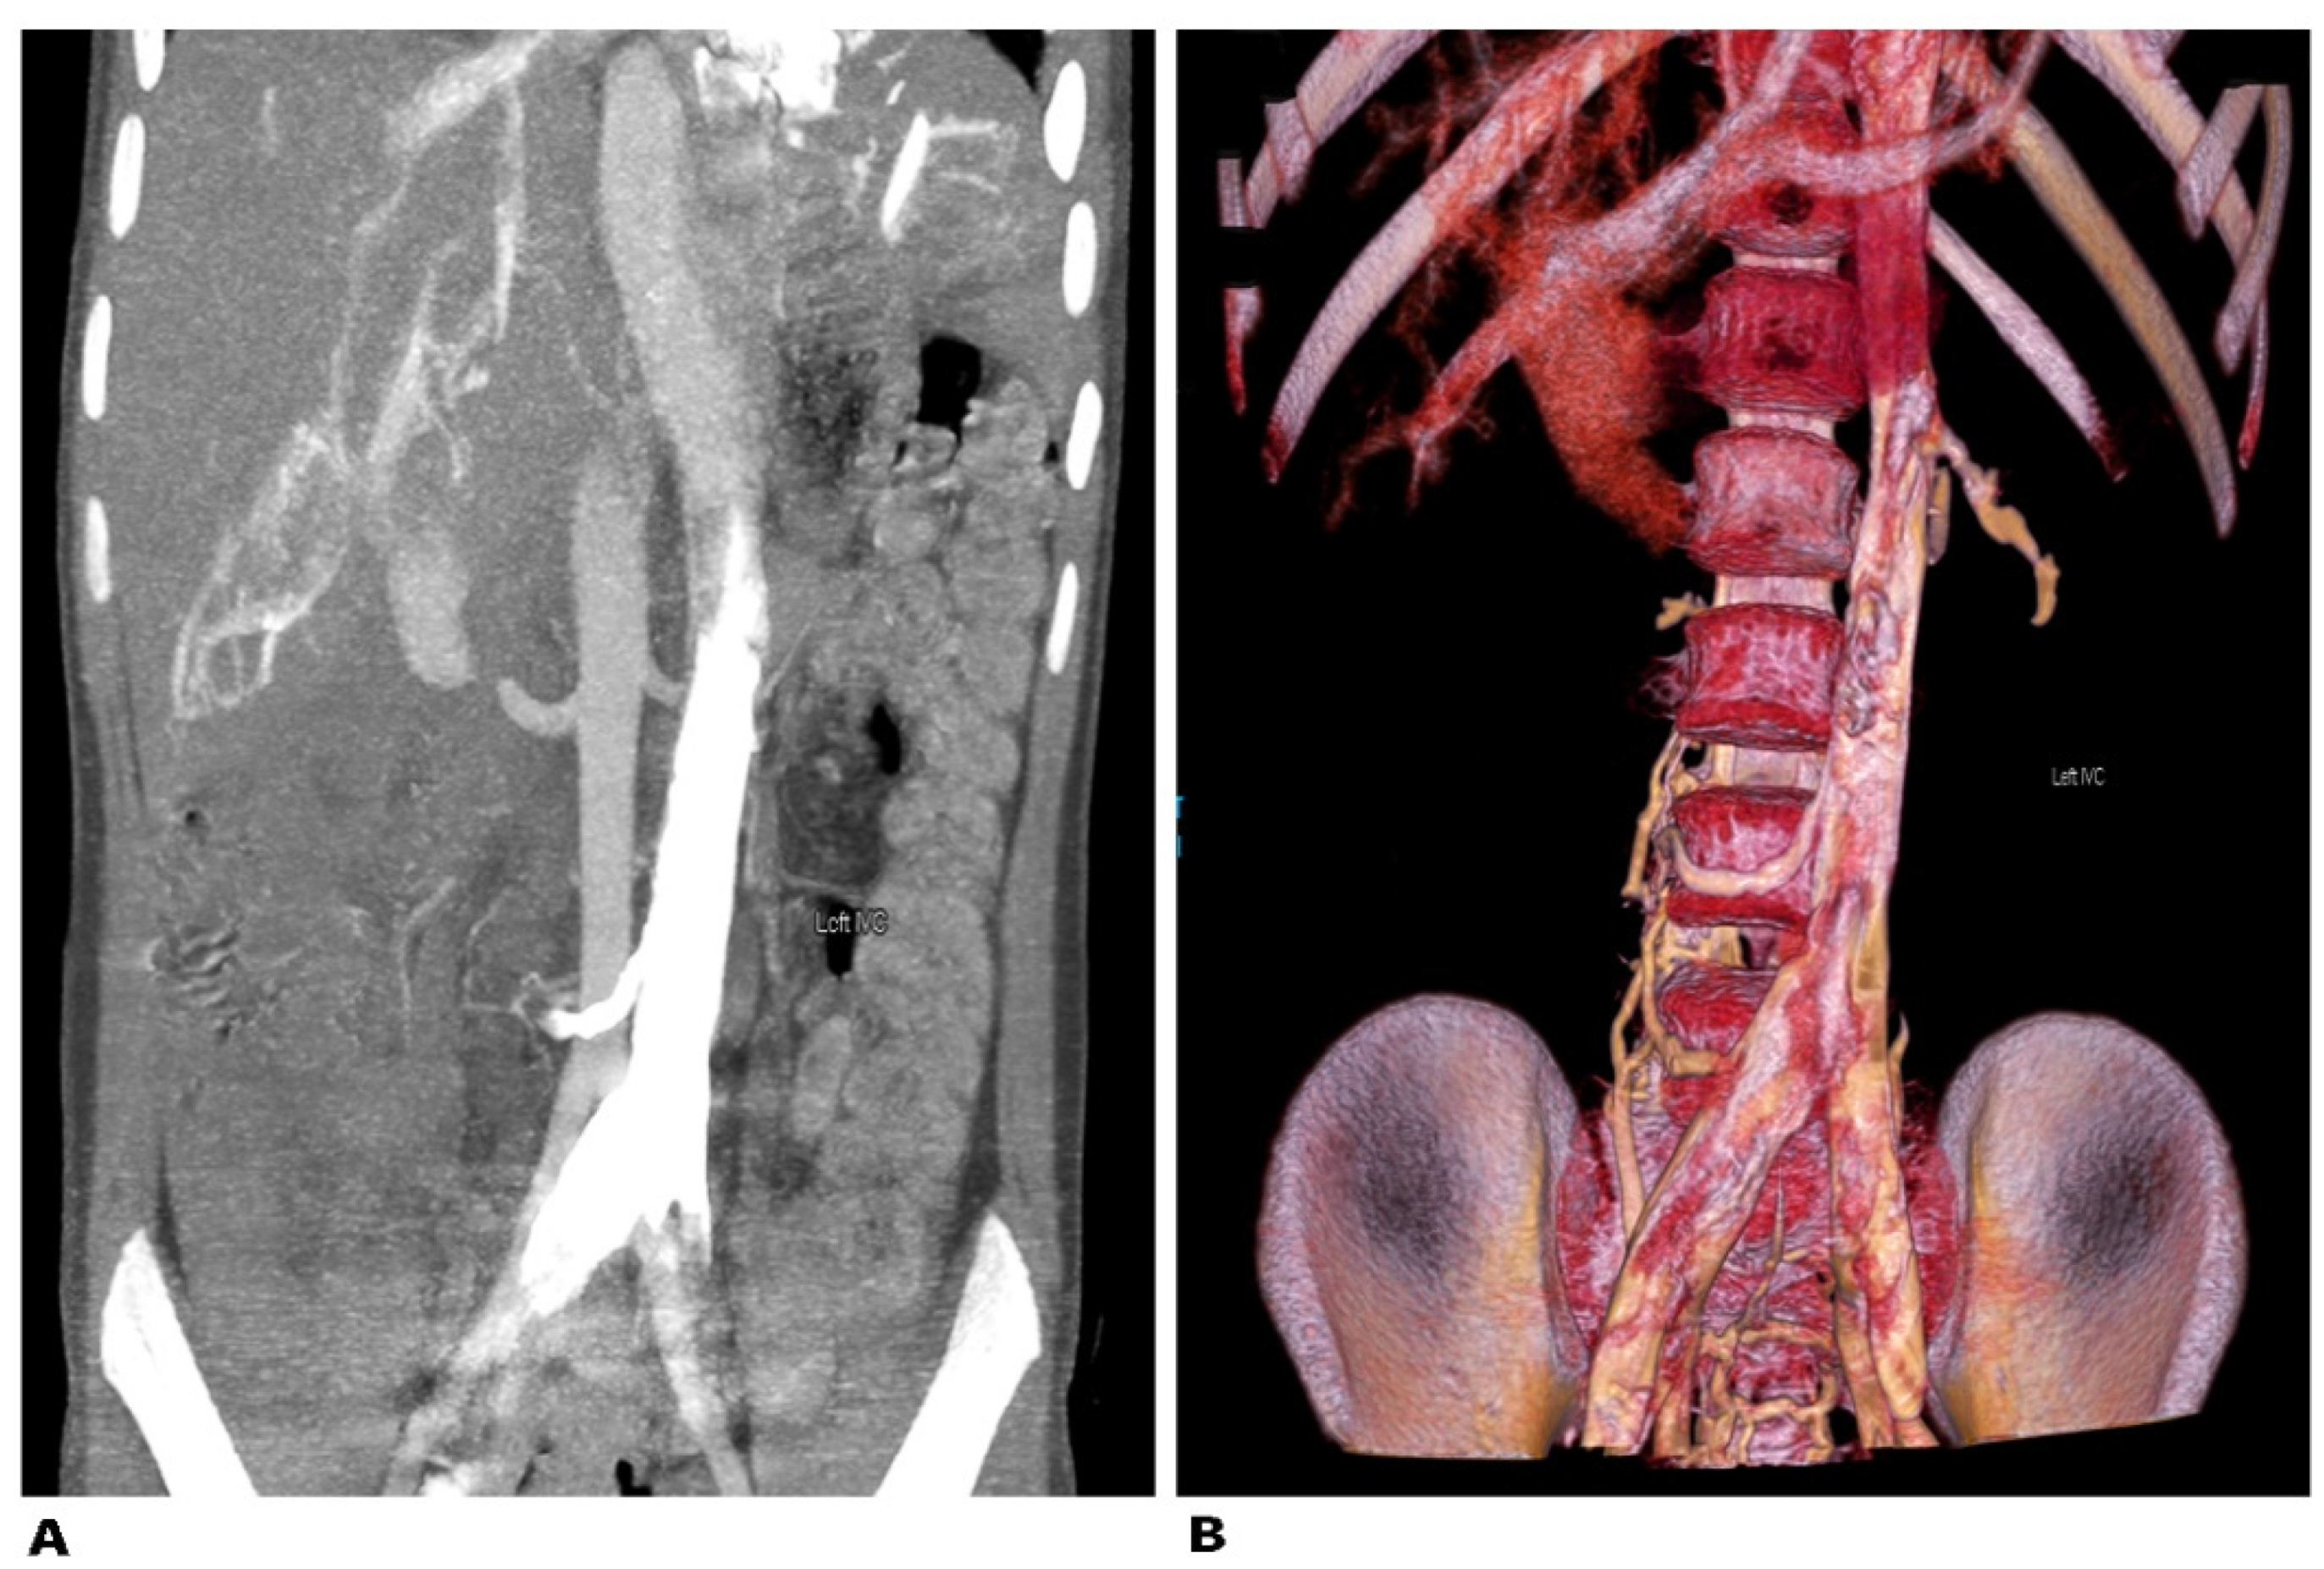

9.4.1. Left Sided Inferior Vena Cava

Surgical Considerations